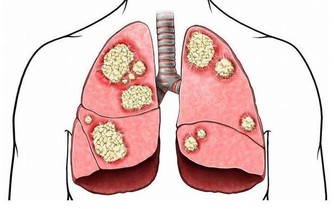

如何做到自我調節

①不吃高嘌呤食物

例如動物肝臟、動物腎臟,還有生蠔、沙丁魚、菠菜、豆類、蘑菇等高嘌呤食物,以及肉湯、火鍋等都要少吃。

②必須戒酒

酒精會讓血液中的乳酸濃度增加,乳酸排泄的時候會影響尿酸的排出,讓尿酸排出減少。同理,咖啡、濃茶等刺激性飲品也要少喝。

③多吃維生素B1含量高的食物

維生素B1含量高的食物、鹼性食物,都有利於痛風患者,因為尿酸可以在鹼性的環境中溶解,減少尿酸結晶的沉積。

④少吃高蛋白食物

蛋白質攝入過多,也會讓體內產生多餘的嘌呤,但是人每天又需要攝入足夠的蛋白質,那麼可以多吃牛奶、雞蛋等食物,或者吃肉不喝湯。

⑤一定多喝水

多喝水可以讓尿液中尿酸濃度降下來,還有利於尿酸的排出,最好每天飲水不少於2000毫升,也可以喝蘇打水,中和尿酸。

⑥控制體重

身材肥胖的人容易得痛風,所以控制好體重顯得很重要,最好能保持運動。